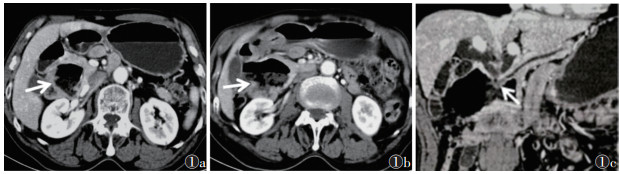

| 注:患者,男,68岁。图 1a为增强扫描门脉期横断面图像,示十二指肠降部巨大憩室(箭头),边界清晰;图 1b为下方层面图像,憩室开口于十二指肠后壁(箭头);图 1c为CPR图像,示憩室压迫十二指肠壶腹部,胆总管及主胰管扩张(箭头) 图 1 十二指肠降部憩室CT图像 |

| 注:患者,男,57岁。图 2a为MinIP图像,示低张下十二指肠肠圈充盈良好(箭头),胆总管壶腹段梗阻;图 2b为CPR图像,病灶呈明显强化软组织密度结节(箭头);图 2c为病理图像,提示胆总管中分化腺癌,镜下肿瘤细胞排列不规则,呈腺管状,纤维间质丰富,细胞核深染,异型性明显(HE染色,高倍放大) 图 2 胆管癌CT及病理图像 |